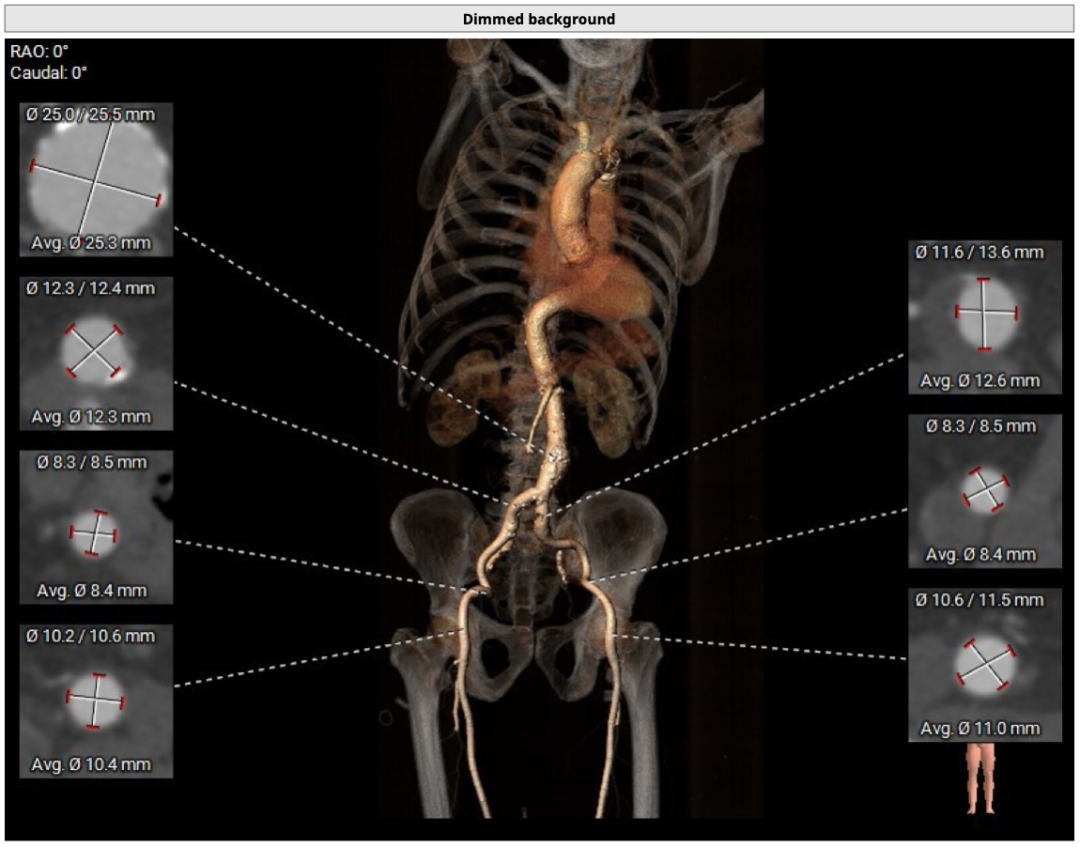

血管外周及入路评估

整体入路血管条件尚可,血管内径可,患者有明显的脊柱侧弯,并伴有腹主动脉瘤,降主动脉稍有扭曲,腹主动脉、降主动脉及弓顶有少许钙化斑块。